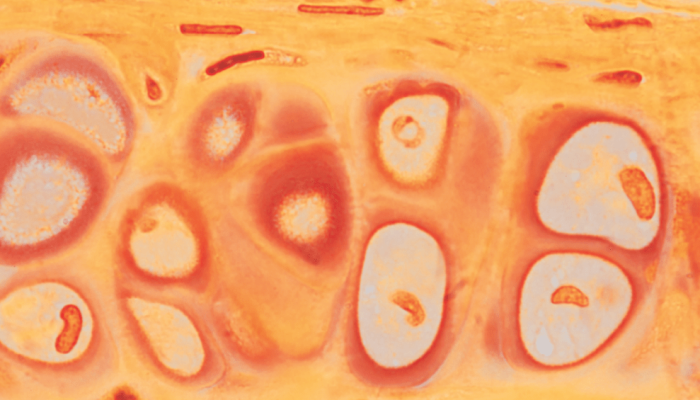

Zoom: um sopro de vida